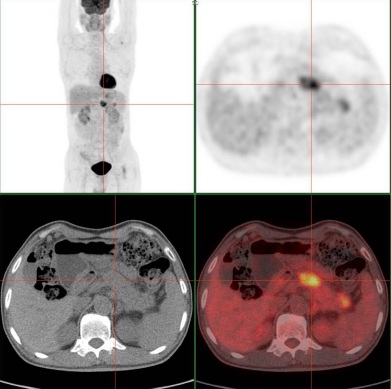

对于刚确诊癌症的患者,PET/CT可以明确肿瘤分期。比如肺癌患者,通过一次扫描就能清楚判断肿瘤是否转移到纵隔淋巴结、肝脏、骨骼等部位,医生据此制定手术、化疗还是靶向治疗的方案。有数据显示,约 20% 的癌症患者通过 PET/CT 检查后,会改变原有的治疗计划。

治疗中的患者也需要定期做 PET/CT 评估疗效。化疗或放疗后,肿瘤是否缩小、活性是否降低,传统检查可能难以准确判断,而 PET/CT 能通过肿瘤细胞对显像剂(如 18F-FDG)的摄取量变化,直观反映治疗效果。如果肿瘤仍有高代谢活性,提示可能需要调整治疗方案。

癌症具有转移特性,有些患者会出现不明原因的骨痛、头痛或体重骤降,怀疑肿瘤转移却找不到具体位置。这时 PET/CT 就能发挥优势,它能一次性扫描全身骨骼、脑部、内脏等部位,精准定位转移灶。例如乳腺癌患者出现腰背痛,PET/CT 可明确是否发生骨转移,比骨扫描更敏感,还能同时排查其他部位的转移情况。